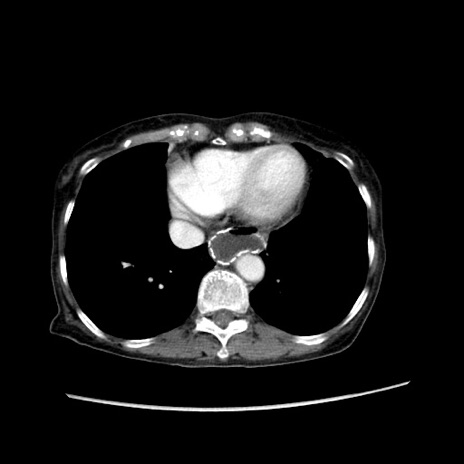

症例25(横断像)

【症例】80歳代女性

【主訴】胸のつかえ感

【現病歴】約9時間前に食後から胸のつかえた感じあり、嘔吐あり、来院。

【既往歴】胃癌(全摘)、胆摘、虫垂炎

【身体所見】心窩部に圧痛あり、反跳痛なし。

【データ】WBC 5700、CRP 0.05